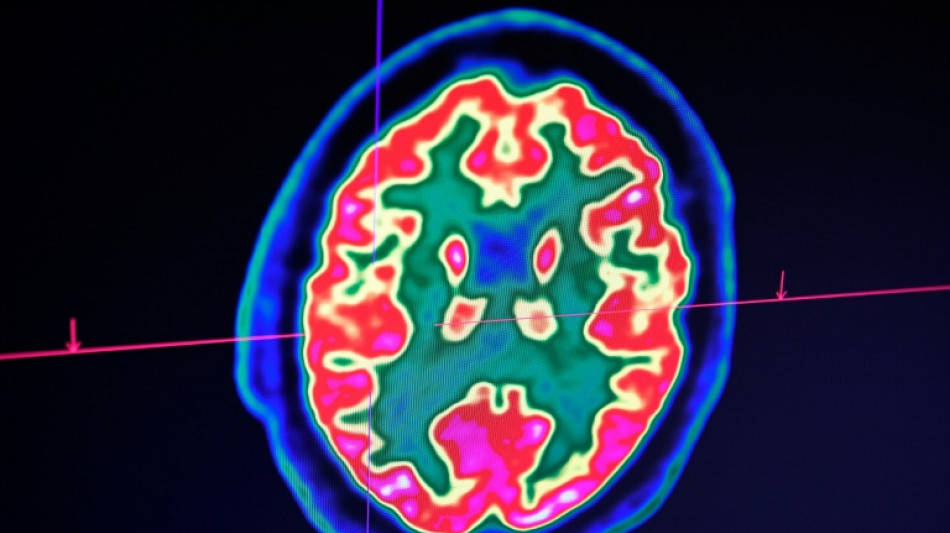

Sclérose en plaques: la découverte d'un lien avec un virus fait espérer une meilleure riposte / Photo: © AFP/Archives

Celle-ci est une maladie auto-immune du système nerveux central (cerveau et moelle épinière). Elle provoque un dérèglement du système immunitaire, qui s'attaque à la myéline, la gaine protectrice des fibres nerveuses.